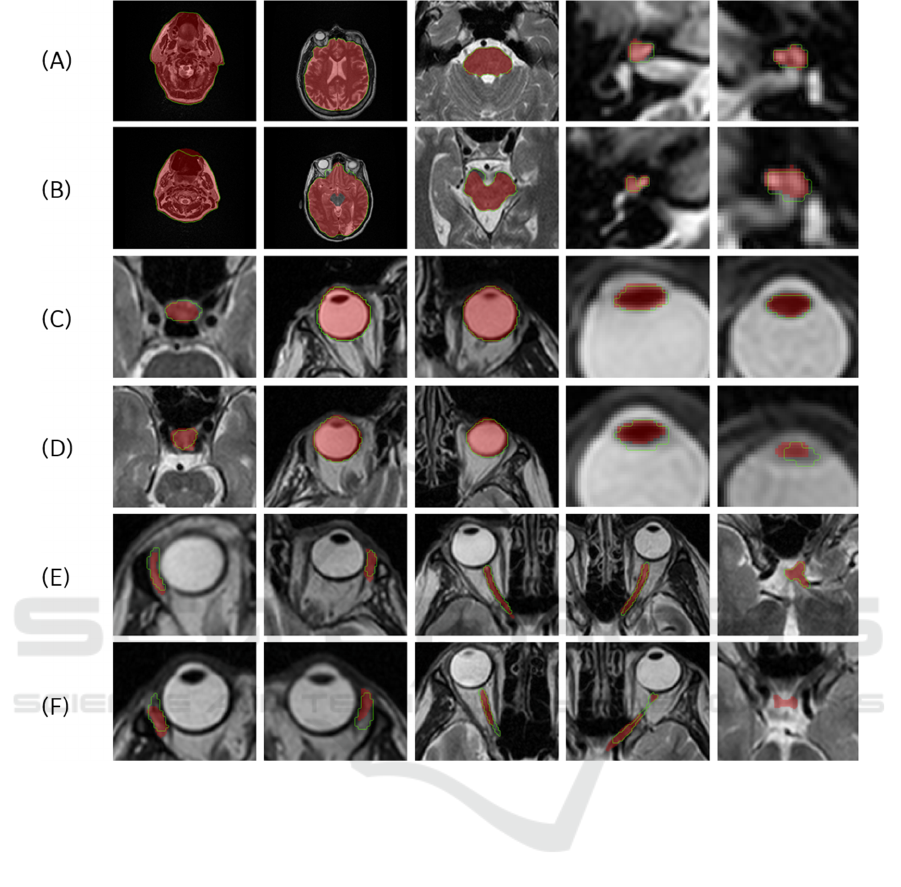

Figure 5 demonstrates the best and the worst 3D

results for all anatomy structures from the 5 test cases

of AAPM dataset. In the images the gold standard is

represented with red overlay, while the model

prediction is shown with green outline. All results are

displayed in the axial views.

Figure 5: The best ((A), (C) and (E)) and worst ((B), (D) and (F)) segmentation results in the axial direction for the 15 OARs

((A) and (B) shows body, brain, brainstem, right and left cochlea, (c) and (D) shows the pituitary gland, right and left eyeball,

right and left lens, (E) and (F) shows right and left lacrimal gland, right and left optic nerve and chiasm). The predicted result

is depicted in green, and the gold standard is shown as a red overlay.